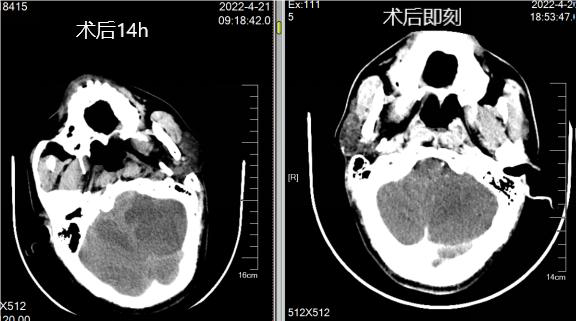

手术过程

1、8F导引导管到位后造影,见右侧颈内动脉起始部闭塞,微导丝及微导管穿过闭塞端,微导管造影确认真腔后,交换出微导管。

病历夹什么径技·第152期|串联营病历夹:川陕大营_https://www.jmylbn.com_新闻资讯_第62张

2、将BostonScientificSterlingMR2.5*20mm球囊置于右侧颈内动脉起始部,将压力打至8个大气压。

病历夹什么径技·第152期|串联营病历夹:川陕大营_https://www.jmylbn.com_新闻资讯_第63张

3、小球囊扩张后见右侧颈内动脉起始部重度狭窄,右侧大脑中动脉分叉处血栓形成。

病历夹什么径技·第152期|串联营病历夹:川陕大营_https://www.jmylbn.com_新闻资讯_第64张

4、使用6F中间导管抽吸后,右侧大脑中动脉血流通畅。

病历夹什么径技·第152期|串联营病历夹:川陕大营_https://www.jmylbn.com_新闻资讯_第65张

病历夹什么径技·第152期|串联营病历夹:川陕大营_https://www.jmylbn.com_新闻资讯_第66张

<<滑动查看下一张图片>>

5、保护伞到位后,使用BostonScientificSterling MR4.0*30mm球囊扩张,将压力打至14个大气压,造影见右侧颈内动脉起始部狭窄扩张满意。

病历夹什么径技·第152期|串联营病历夹:川陕大营_https://www.jmylbn.com_新闻资讯_第67张

6、右侧颈内动脉起始部置入Carotid WALLSTENT7*40mm自膨式支架,造影见:支架贴壁良好,斑块完全覆盖,血流通畅,管腔打开良好,右侧大脑中动脉血流通畅。支架置入后观察30分钟,支架内血流通畅。

术后情况

• 术后第一日情况:患者意识呈清醒状,自动睁眼,言语不利。双侧瞳孔等大等圆,直径约3.0mm,对光反射灵敏。左侧肢体肌力IV级。

• 术后第二天复查CT,外渗造影剂吸收。

• 术后第三天复查CT,外渗造影剂进一步吸收。

• 术后第九日情况:患者意识呈清醒状,自动睁眼,言语基本流利。双侧瞳孔等大等圆,直径约3.0mm,对光反射灵敏。左侧肢体肌力IV级。